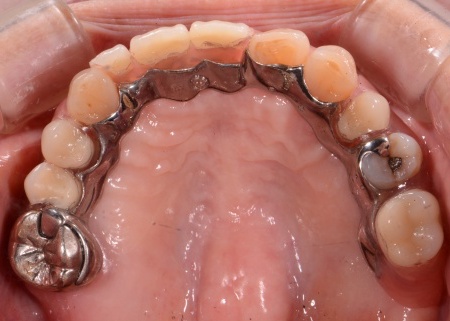

60代女性 金属のバネを使用しない入れ歯を作製した症例

拝見したところ、上の前歯を含め数本の歯が欠損していました。

保険診療で作製される入れ歯の多くには、入れ歯の浮き上がりや脱落を防ぐために周囲の歯に引っかける金属製のバネ(クラスプ)が付いています。

とくに今回のように前歯が欠損している場合、クラスプが隣接する前歯にかかるため見た目に影響することがあります。

そこで今回は、金属のバネを使用しないノンクラスプチタンデンチャーを提案し、同意いただきました。

ノンクラスプチタンデンチャーは自由診療のため保険診療より費用はかかりますが、歯に引っかける部分を歯ぐきに近い色の樹脂で作ることで、より自然な見た目を実現できます。

さらに外から見えにくい部分に金属を使用することで、保険の入れ歯よりも薄くて丈夫になり装着時の違和感を軽減できます。